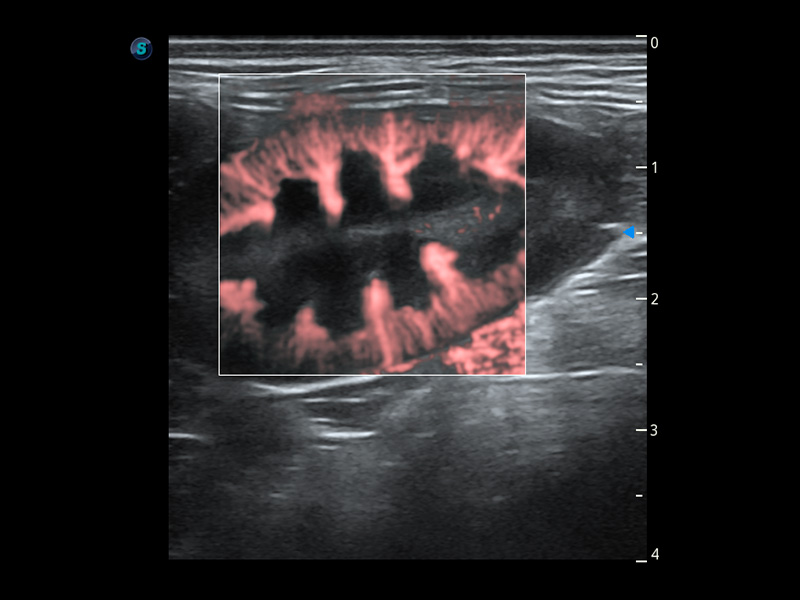

ProPet 60 作为一款高端台式动物超声设备,为动物医生的日常诊断提供了一系列贴合动物临床需求、解决临床实际问题的高级成像功能。凭借全系列高清探头,满足医生对腹部、心脏、生殖、浅表、肌骨等成像的所有需求,切实帮助您提升检查效率,提高诊断信心。

兽用彩色多普勒超声诊断系统